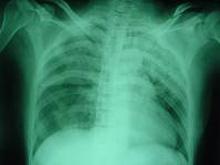

概述:膈扑动(Flutter of the Diaphragm)系指因膈肌阵发性或持续性痉挛,伴有吸气期声门突然关闭,产生一种短促奇特的声音、令人不能自制的一种症状。按痉挛轻重分为呃逆(Hiccup)、膈肌痉挛(Phrenospasm)、膈肌扑动。膈肌扑动少见,当其发作时,膈肌有极快的而有节奏的收缩,每分钟可达100~300次。